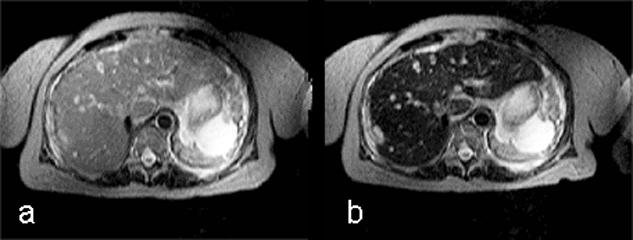

Although the chemical composition of Gd-BOPTA appears similar to that of the extracellular gadolinium agents, it combines both extracellular and liver-targeted properties, because some 5% of it is excreted through the liver, as is shown in this case of multiple metastases (Figure 13-14).

Figure 13-14:

Gadolinium-BOPTA in liver metastases of a pancreatic tumor.

(a) plain T1-weighted GRE sequence; (b) plain T2-weighted GRE sequence; (c) enhanced T1-weighted GRE sequence 40 minutes after injection; (d) T1-weighted GRE sequence 90 minutes after injection.